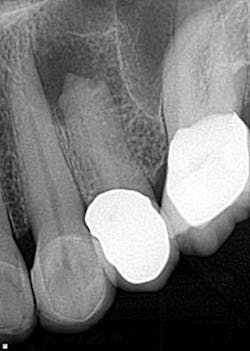

Case report A healthy 61-year-old female presents with a chief complaint of pain and discomfort in the upper left quadrant. A radiograph revealed a large radiolucency at the apex of tooth No. 12. An irregular root apex was also noted. Clinically No. 12 was sensitive to percussion and palpation in the buccal vestibular area. There was no response to cold. Diagnosis was necrotic tooth No. 12 with associated periapical abscess. RCT was recommended and the patient was referred to a specialist for completion. RCT was completed — no complications were noted and the prognosis was given as good. (Figs. 1 and 2) The patient was placed on recall by the endodontist for reevaluation of the lesion in 12 months.Fig 1. Fig. 2Eight months later, the patient presented back to the office stating that she felt pressure again in the upper left area. A radiograph of No. 12 showed an increased radiolucency around the apex of tooth No. 12. Furthermore, there was a draining fistula in the buccal vestibule. Diagnosis was persistent infection/disease, likely due to the initial presentation and presence of the cyst. (Fig. 3)